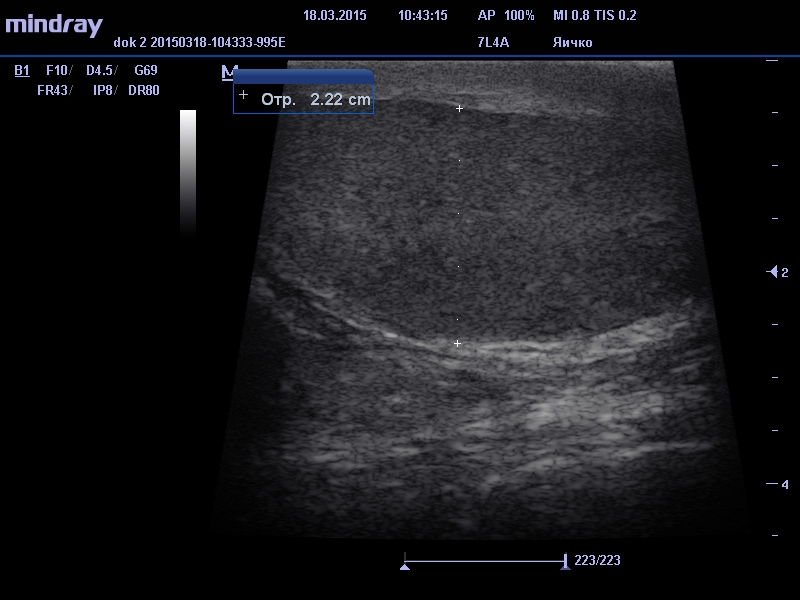

Данный метод диагностики позволяет определить размеры, структуру яичек и их придатков, наличие свободной жидкости, её количество и характер, измерить диаметр вен т.н. лозовидного сплетения с определением характера кровотока в них и правильности работы клапанного аппарата вен.

- опухоли – могут быть обнаружены в яичке и придатке, бывают доброкачественными и злокачественными, длительно могут развиваться без проявления боли и поэтому очень важна диагностика на ранних этапах. УЗИ органов мошонки позволяет обнаружить даже опухоль малых размеров, которую невозможно пропальпировать.